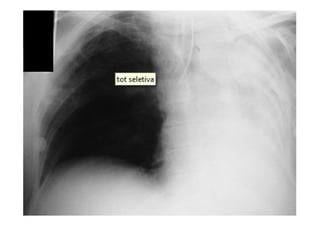

Radiografia e TC de tórax

Utiliza-se com frequênciap/ avaliar: O posicionamento do TOT: 4-6 cm acima da carina; Se os pulmões estão sendo aerados adequadamente; Alterações patológicas e diagnóstico de pneumopatias; Outros. Radiografia e TC de tórax